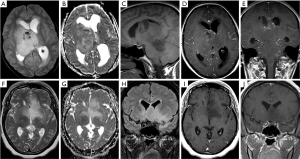

An overview of conventional imaging features is shown in Table 3. All H3 K27M-mutant gliomas were in contact with the brain midline (Figure 3). The lesion volumes ranged from 9.2 to 103.1 cm3. The definition of the non-contrast enhancing tumour margin appeared variable, whereby most lesions demonstrated heterogeneous T2/FLAIR signal. The observed T2/FLAIR heterogeneity corresponded to visible differences in ADC signal, with facilitated diffusion shown in necrotic glioma components. None of the H3 K27M histone-mutant gliomas exhibited a T2-FLAIR mismatch sign. Several tumours contained haemorrhagic components (Figure 4), whereas calcification was not identified, and only two tumours contained cysts. Rim-enhancement surrounding necrosis was present in 10/15 (67%) gliomas; 6/15 (40%) patients required shunting for hydrocephalus. Two gliomas were imaged with dynamic susceptibility contrast enhanced (DSC) perfusion MRI (Figure 5), which revealed elevated relative cerebral blood volume (rCBV) indicative of neovascularity. In one case, 18F-choline PET imaging was performed, showing radioactive tracer accumulation within enhancing tumour components (Figure 6).

Variable T2/FLAIR characteristics, tumour border definition and contrast patterns were encountered, with solid and rim enhancement patterns coexisting. T2 hypointense glioma regions tended to correspond to low ADC signal in keeping with features previously reported for DIPG anaplastic components (42). Haemorrhage was evident in one third of cases, which has been hypothesised to represent a specific feature of H3 K27M-mutant gliomas in the cord (43). The diversity of glioma features and lesion volumes may reflect discovery at different time points during the disease, as suggested by the serial morphology change in case 7. High genomic instability has been discovered in histone-mutant gliomas (7), which may be associated with complex lesion architecture and imaging changes over time.